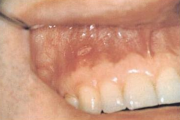

B vitamiini puudus